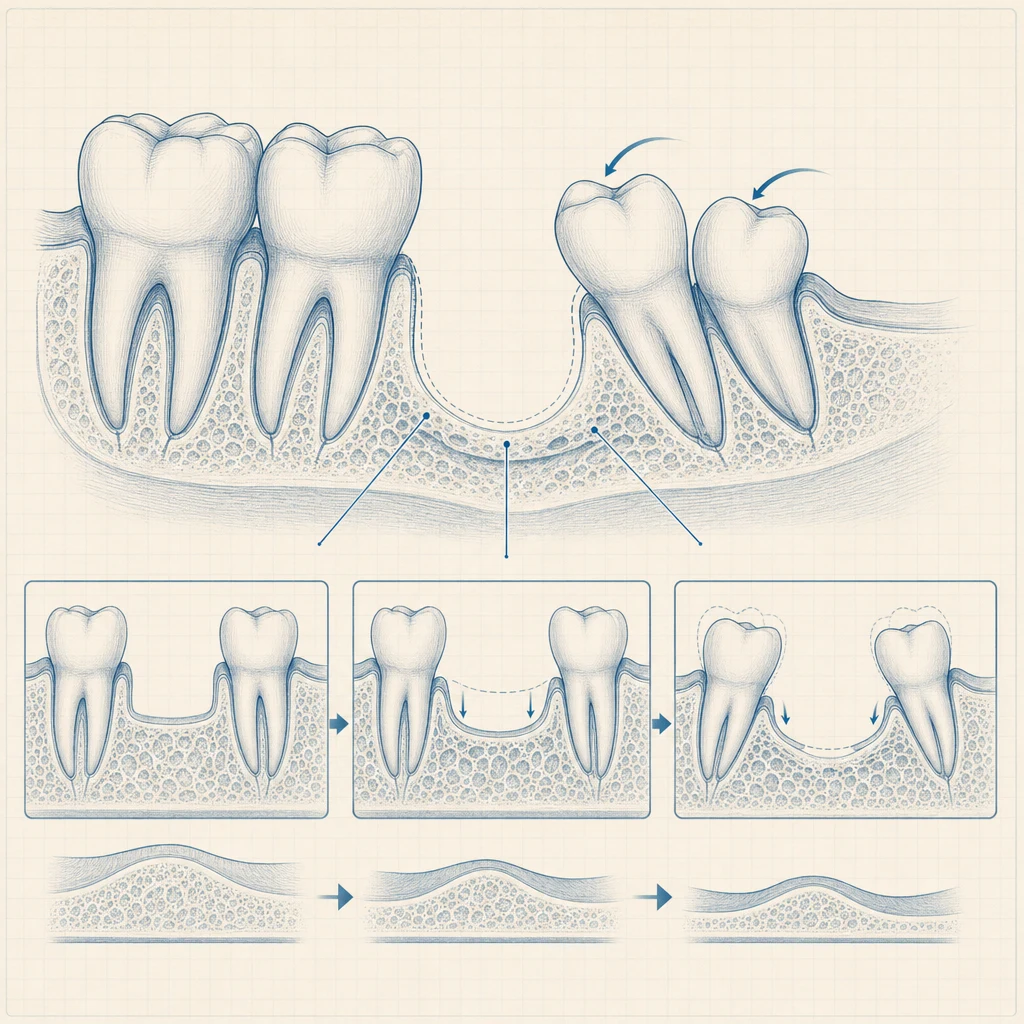

발치 또는 결손치 자리를 그대로 둘 수 없는 이유부터 정리하면:

- 인접 치아의 기울어짐: 빈 공간 쪽으로 옆 치아가 6개월 이내 기울어집니다.

- 대합치 정출: 위·아래 마주보는 치아가 빈 공간으로 솟아오릅니다.

- 잇몸뼈 흡수: 사용하지 않는 치조골은 시간이 지날수록 줄어듭니다.

대안으로 브릿지(양옆 치아를 갈아 다리처럼 잇는 방식) 또는 부분틀니가 있지만, 양옆 자연치아를 보존하면서 빈 공간만 회복하는 점에서 임플란트가 장기적으로 가장 보존적입니다.